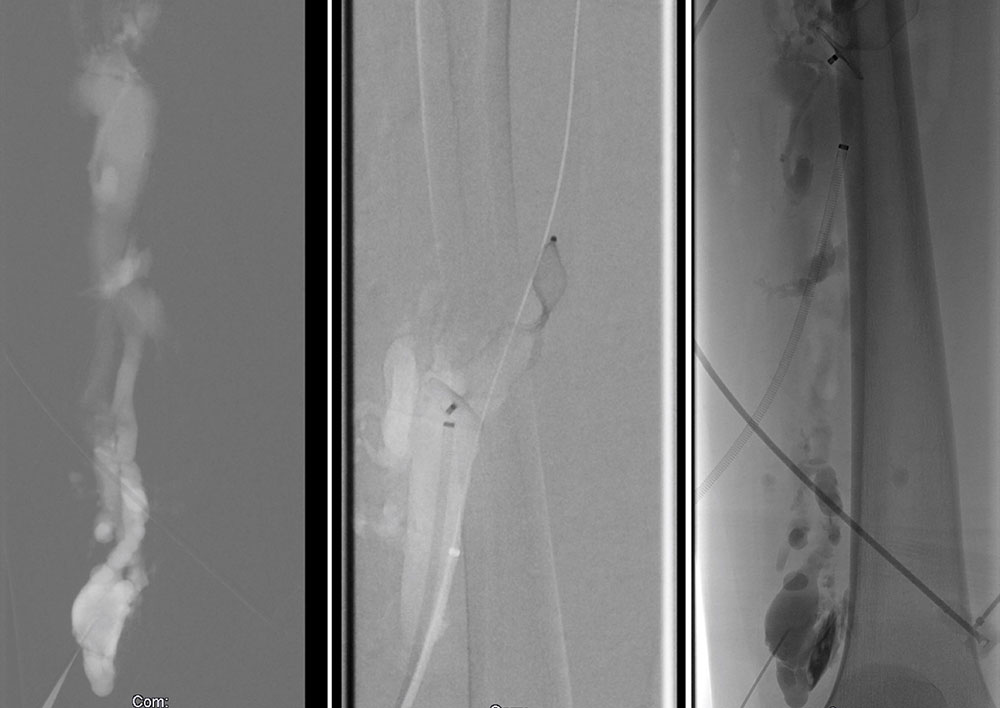

Phlebography has been almost entirely replaced by ultrasound, CT or MR phlebography for the diagnosis of phlebothrombosis and is no longer indicated. Phlebography nowadays is mostly performed as varicography in the direct puncture technique in the context of interventional procedures. In this situation the thrombus is visualized as an intraluminal contrast medium filling defect in the vein.

Invasive measures today often include minimally invasive, catheter-guided mechanical or pharmacomechanical procedures. In these procedures, the acute thrombus is dissolved by mechanical or pharmacomechanical catheter therapy in a minimally invasive manner. Chronic occlusion, especially in the iliofemoral location descending from an iliac vein, can also be reopened minimally invasively, and stents are usually implanted. Open surgical therapy of acute thrombosis is very rarely indicated today, primarily in cases of iliofemoral thrombosis with occlusion of the pelvic venous circulation, and may be combined with creation of an arteriovenous fistula in the groin to keep the reopened vein open. However, appropriate measures should always be performed at a center.